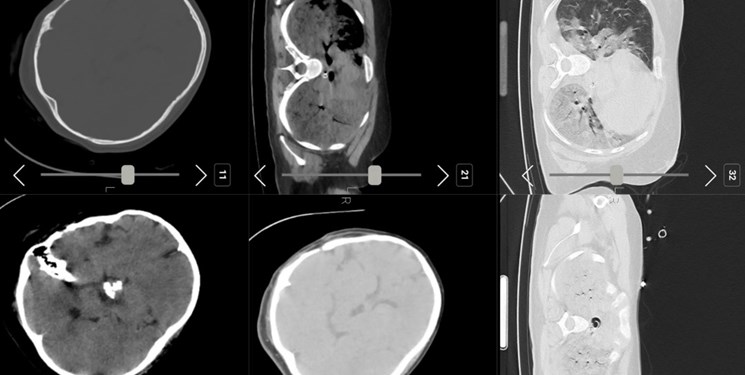

فارس نوشت: صبح امروز شبکه اینترنشنال عکسی از سیتی اسکن مرحوم مهسا امینی منتشر کرد و مدعی شد که «سیتی اسکن مهسا نشانگر شکستگی جمجمه، خونریزی و ادم مغزی است».

با اینکه در ابتدا تصور می شد این تصاویر جعلی باشد اما پیگیری ها از مراجع ذیربط نشان داد تصاویر سیتی اسکن منتشر شده مربوط به مرحوم مهسا امینی است.

برای بررسی علمی این موضوع با تعدادی از پزشکان مغز و اعصاب و رادیولوژیست گفتوگو کردیم تا به صورت علمی این موضوع را بررسی کنیم. این متخصصان معتقدند بررسیهای سی تی اسکن بیمارستان نشان میدهد هیچ شواهدی از ضربه به سر و خونریزی در این تصاویر به چشم نمیخورد.

یک متخصص جراحی مغز و اعصاب گفت: بررسیها نشان میدهد که بیمار در گذشته جراحی در ناحیه سر انجام داده است اما براساس شواهد موجود از روی سیتیاسکن نمیتوان فهمید که جراحی دقیقاً مربوط به چند سال قبل است.همچنین شواهد کرانیتومی فرونتوتمپورال قبلی همراه با آتروفی مختصر عضلانی و تغییرات بافت نرم در محل جراحی بیمار مشهود است.

یکی دیگر از پزشکان مغز و اعصاب نیز جراحی تومور بیمار را تایید میکند. به گفته این متخصص مغز و اعصاب متاسفانه برخی از افراد با دیدن تصاویر ناقص سی تی اسکن درفضای مجازی اقدام به اعلام نظر کردهاند اما واقعیت این است که در تصاویر کامل اثری از شکستگی نیست و این رسانه سعودی تصاویر را از زاویهای منتشر کرده است که شکستگی به نظر برسد.

برای بررسی دقیقتر موضوع با یکی دیگر از پزشکان نیز گفتوگو کردیم که این متخصص مغز و اعصاب در این خصوص میگوید: بیمار در گذشته جراحی سر انجام داده و بخشی از تومور در ناحیه سوپراسلار باقی مانده است. بررسی بیشتر سی تی اسکن بیانگر این است که با توجه به نوع جراحی انجام شده در این ناحیه وقوع دیابت بیمزه در بیمار دور از انتظار نیست و با توجه به آتروفی لوب فرونتال راست احتمال صرع را نمیتوان برای بیمار رد کرد هرچند اساساً تشخیص صرع یا دیابت بیمزه با سیتیاسکن مقدور نیست.

برای بررسی وضعیت ریه بیمار نیز با تخصص رادیولوژی گفتوگو کردیم که وی توضیح میدهد: در سیتیاسکن ریه شواهد کانتیوژن یا له شدگی بافت ریه مشاهده میشود که پس از «سی پی آر» رخ میدهد و ممکن است در هر بیماری رخ دهد و این موضوع غیرطبیعی نیست.